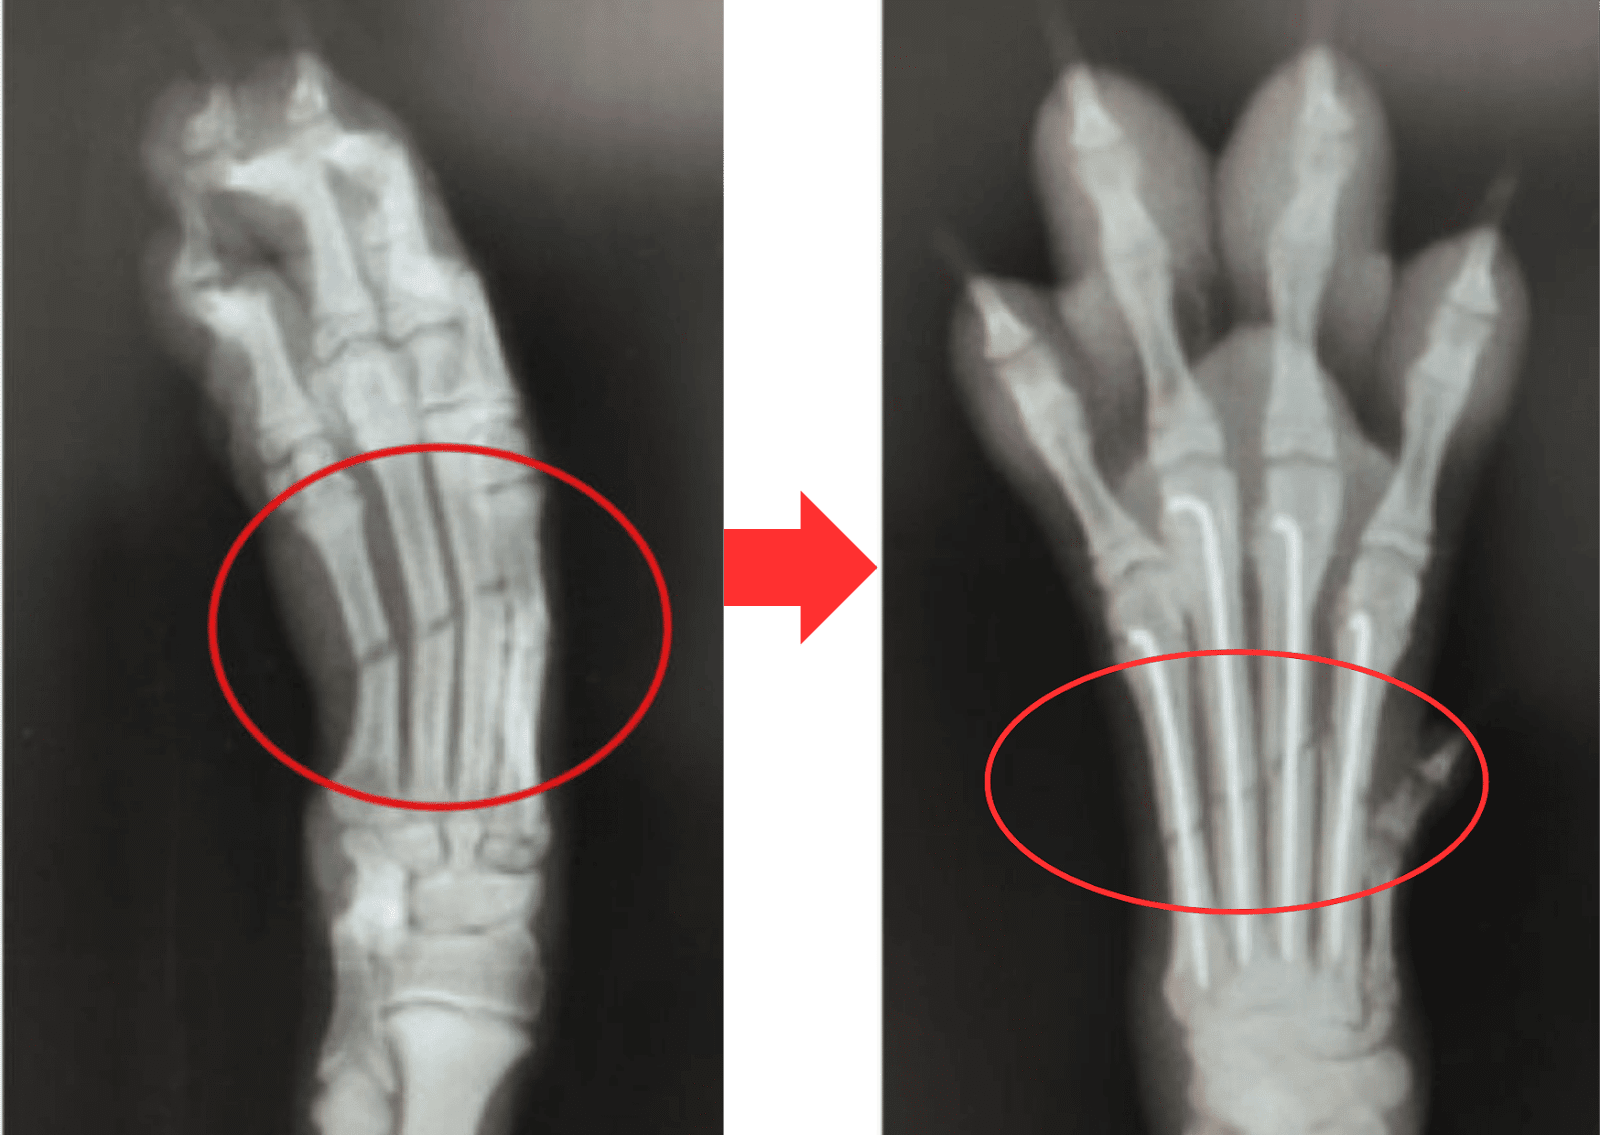

手術では、ずれてしまった骨を本来の位置に戻し、Kワイヤー(細いステンレス製の針金)やプレート、スクリューなどの金属製の器具を使って、骨をしっかりと固定します。

実際に当院で行った症例では、4本の骨が骨折していたため、Kワイヤーによる整復を行いました。

術前のレントゲンでは、骨折によって骨が大きく曲がっていましたが、手術後にはまっすぐな状態に整えられていることが確認できました。